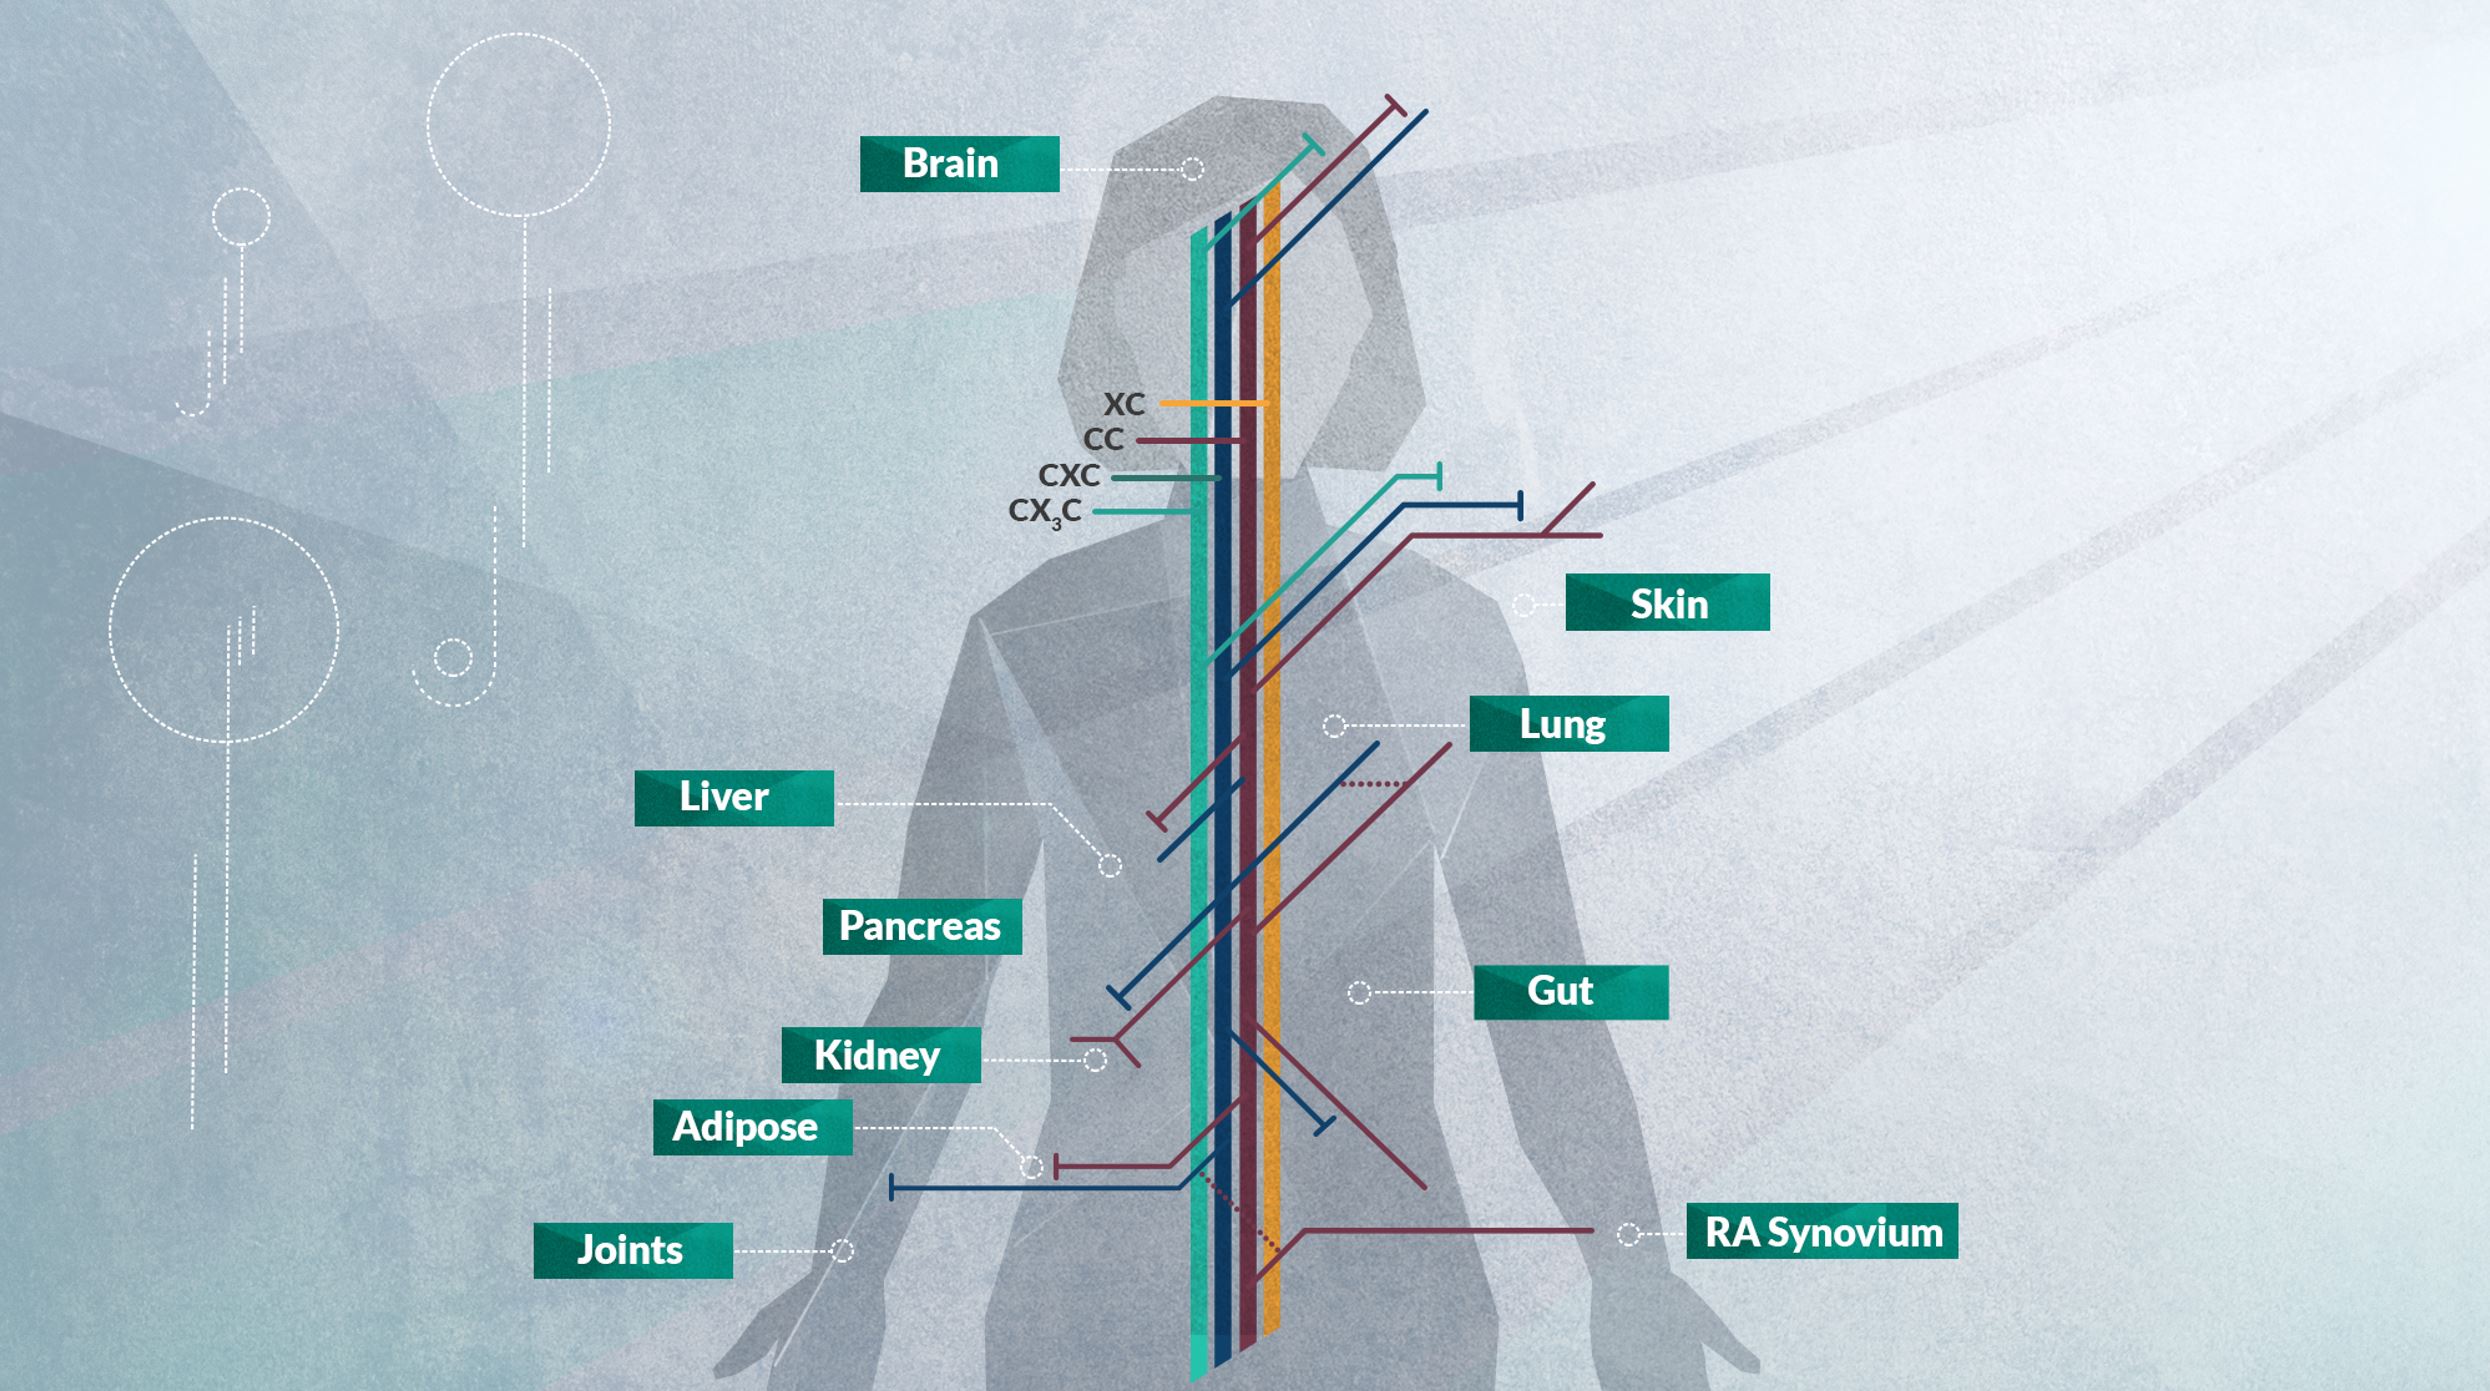

ChemoCentryx